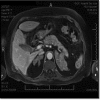

Summary: PBMAH is a rare etiology of Cushing syndrome (CS). Familial clustering suggested a genetic cause that was recently confirmed, after identification of inactivating germline mutations in armadillo repeat-containing 5 (ARMC5) gene. A 70-year-old female patient was admitted due to left femoral neck fracture in May 2014, in Orthopedics Department. During hospitalization, hypertension (HTA) and hypokalemia were diagnosed. She presented with clinical signs of hypercortisolism and was transferred to the Endocrinology ward for suspected CS. Laboratory workup revealed: ACTH <5 pg/mL; urinary free cortisol (UFC), 532 µg/24 h (normal range: 20-90); failure to suppress the low-dose dexamethasone test (0.5 mg every 6 h for 48 h): cortisol 21 µg/dL. Abdominal magnetic resonance imaging (MRI) showed enlarged nodular adrenals (right, 55 × 54 × 30 mm; left, 85 × 53 × 35 mm), and she was submitted to bilateral adrenalectomy. In 2006, this patient's 39-year-old daughter had been treated by one of the authors. She presented with severe clinical and biological hypercortisolism. Computed tomography (CT) scan showed massively enlarged nodular adrenals with maximal axis of 15 cm for both. Bilateral adrenalectomy was performed. In this familial context of PBMAH, genetic study was performed. Leucocyte DNA genotyping identified in both patients the same germline heterozygous ARMC5 mutation in exon 1 c.172_173insA p.I58Nfs*45. The clinical cases herein described have an identical phenotype with severe hypercortisolism and huge adrenal glands, but different ages at the time of diagnosis. Current knowledge of inheritance of this disease, its insidious nature and the well-known deleterious effect of hypercortisolism favor genetic study to timely identify and treat these patients.